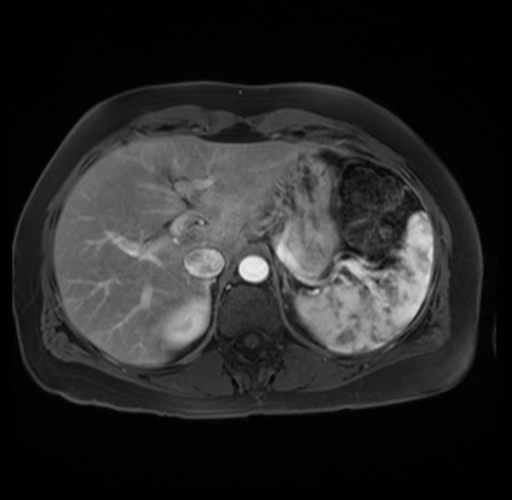

Imaging Analysis

Look through the patient's CT scan to identify any areas of concern for the necessary procedure.

Based on your CT findings, which issue(s) are present and would give reason for "planned slowing down moment(s)" in this case?